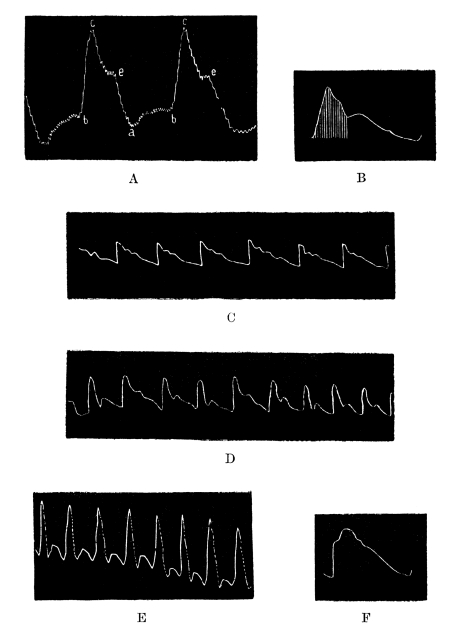

| 15. | Blood-Pressure Tracings | 245 |